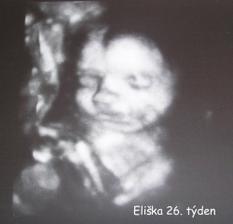

18.září jsme byli na našem 1.IVF... a 8.den od ET se mi "zjevily" nádherné // 🙂... přeju si,aby se všechno vyvíjelo dobře... 29.9 11.den po ET mi pro zhoršení OHSS provedli punkci Douglasova prostoru a odsáli 2 litry žlutého ascitu ☹ Nicméně se mi ulevilo 🙂 HCG ten den 259... 6.10 kontrola HCG - 2950 (18.den od ET)... 10.10 UTZ - čekáme DVOJČÁTKA 🙂 🙂 🙂... 17.10 krvácení a následná hospitalizace, UTZ - dvojčátkům bijí srdíčka, 20.10 HCG - 56000, 25.10 propuštění z nemocnice... 31.10 poslední kontrola v CARu, dvojčátka mají 2 a 2,1 cm... 11.11 UTZ - dvojčátka mají 3 cm... 24.11 UTZ - dvojčátka mají 9 cm (ale moc se mi to měření nezdá, ve čtvrtek na screeningu se ukáže pravda, čeká nás 3D 🙂) 27.11 screening I.trimestru - miminka jsou zdravá, od hlavičky po prdelku mají 7 cm... 19.12 3D - miminko "A" je chlapeček, "béčko" chce zůstat zatím v utajení 🙂 tak snad příště 🙂... 8.1 3D - miminko "B" je holčička 🙂 19.1 echokardiografie - obě srdíčka jsou zdravá 🙂 20.1 screening II.trimestru - vše OK, miminka mají 360 a 364 gramů 🙂 26.1 UTZ - chlapečkovi se ztratil pindík a najednou čekáme 2 holčičky 🙂) Doufám, že už je to definitivní 🙂) 19.2 UTZ 3D4 - holčičky potvrzeny!!! 🙂 mají každá téměř 800 gramů! 🙂 20.3 UTZ - holčičky mají 1700 a 1800 gramů! 8.4 UTZ - holky mají neuvěřitelné váhy 2415 a 2600 gramů! 11.5 nástup do nemocnice... 11.května ve 20,03 se nám akutním císařským řezem narodila Eliška (2970/48) a o minutu později Nelinka (3200/50).Jsme nejšťastnější rodiče na světě! 🙂